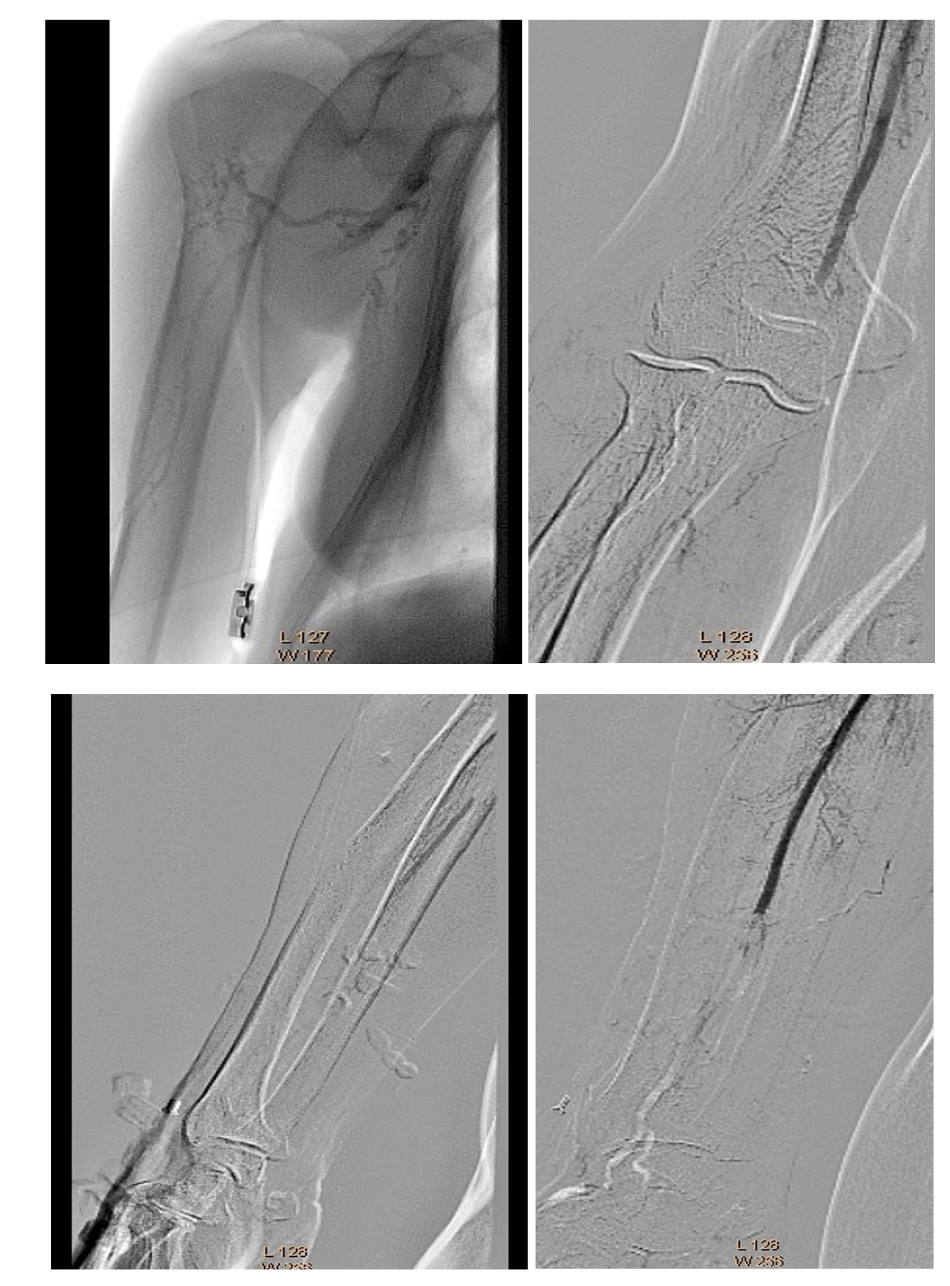

A 6 Fr/90 cm Fortress introducer sheath (Biotronik) was placed at the right subclavian artery (Figure 3). Recanalization was done with a 0.018" Glidewire Advantage (Terumo) and a Trail Blazer Angled Support Catheter (Medtronic) (Figure 4). Balloon dilatations were done with a 2/120 mm Passeo-18 (Biotronik) and a 3/120 mm Passeo-18, without effect (Figure 5). Then, a 0.014" Fielder wire (Asahi) was placed to the palmar arch. Thromboaspiration of red thrombotic masses was done with a 6 Fr Eliminate aspiration catheter (Terumo). Again, there was no distal flow.

A 0.035" Storq wire (Cordis) was then placed in the right radial artery. Effective EVT with a 2.06 mm AngioJet Solent Omni was performed, first in the right brachial artery, then in the axillary artery (Figure 6). The brachial artery was successfully recanalized, but distal embolization in the brachial artery bifurcation occurred again. We repeated EVT with the same 2.06 mm AngioJet Solent Omni in the brachial and radial arteries. Blood flow was restored in the right brachial and radial arteries (Figure 7).